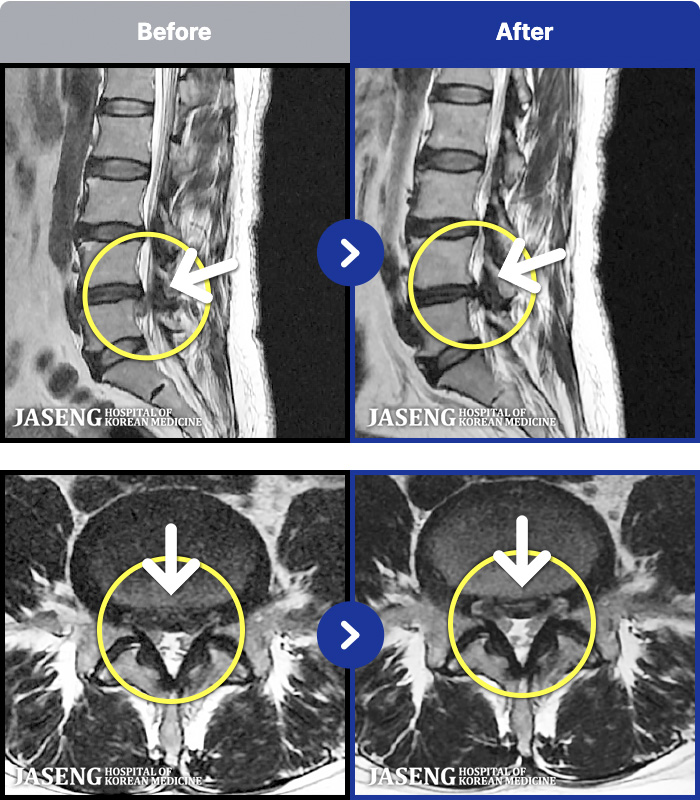

MRI ġ

88 MRI ũ ʸ Ȯϼ.

㸮 ϻ .